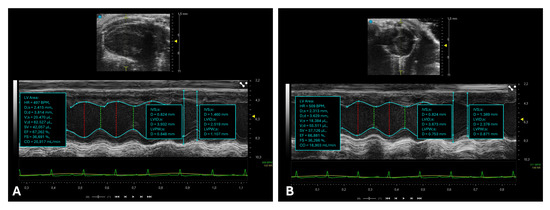

Systole represents the phase of myocardial contraction during which blood is ejected from the cardiac chambers into the circulation [21]. Key parameters used to quantify systolic function include the ejection fraction (EF) and fractional shortening (FS) (Figure 2) [22,23,24].

Assessment of left ventricular systolic function in mice. This figure illustrates echocardiographic assessments of left ventricular systolic function in mice using M-mode ultrasound imaging. (A) M-mode echocardiogram with measurements of left ventricular dimensions during systole and diastole, acquired from a parasternal long-axis (PLAX) view. (B) M-mode echocardiogram with measurements of left ventricular dimensions during systole and diastole acquired with a PSAX view.

The LVIDd and LVIDs measurements of the LV are performed using M-mode echocardiography, in the PLAX (Figure 2A) and PSAX (Figure 2B) view, at the level of the papillary muscles.

The image is first acquired in the B-mode to correctly identify the section, then the M-mode is activated by placing the cursor so that it crosses the center of the left ventricle, perpendicular to the anterior and posterior walls.

End-diastole is the moment when the LV is most dilated, just before contraction, and corresponds to the peak of the R wave on the ECG. LVIDd is measured from the anterior endocardium to the posterior endocardium at the end of diastole. End-systole is the moment of maximum contraction of the ventricle, when it has the smallest diameter, at the end of systole. LVIDs is measured from the anterior endocardium to the posterior endocardium at the end of systole. The measurements are expressed in millimeters (mm).